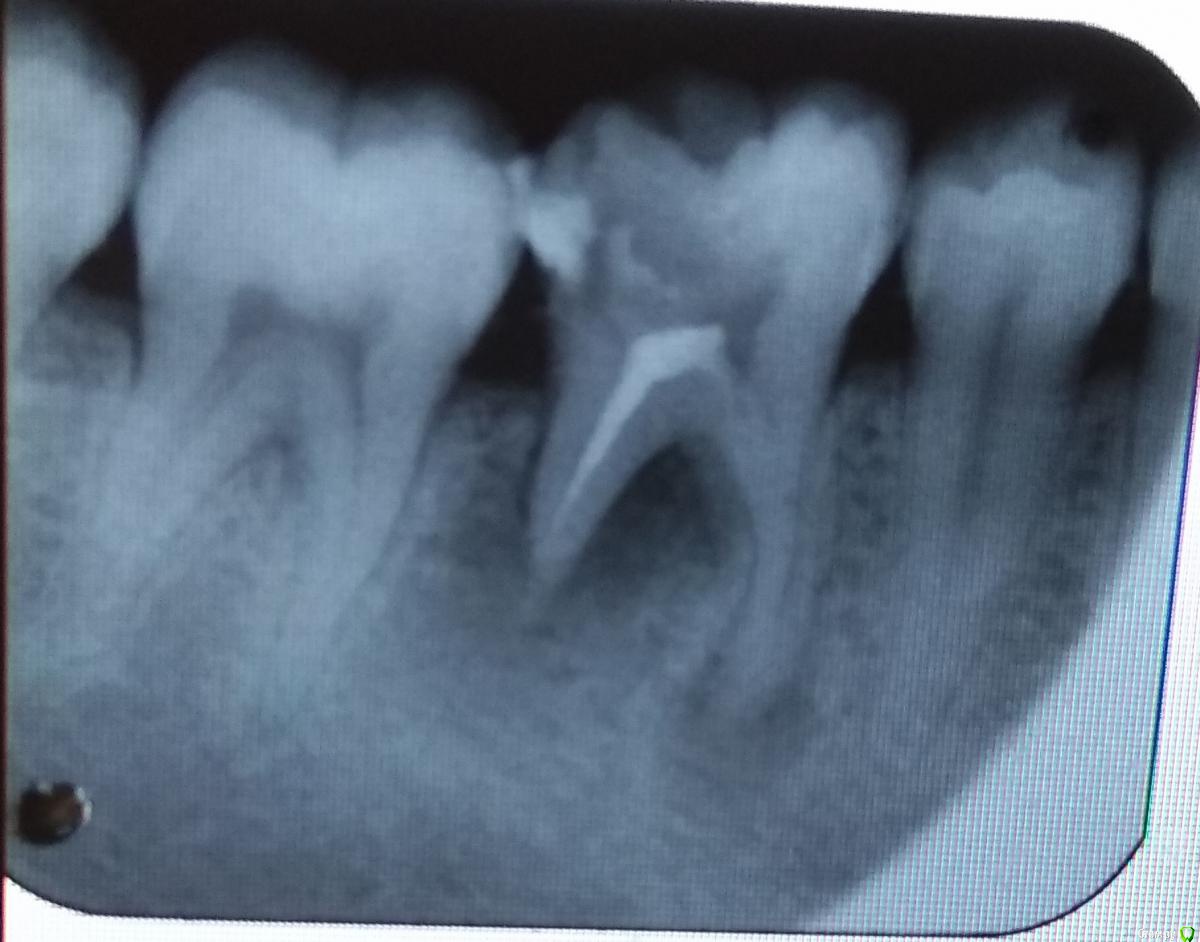

Андре931 Опубликовано 2 октября, 2017 Поделиться Опубликовано 2 октября, 2017 Добрый день уважаемые доктора!Подскажите, возможно ли сохранение зуба и лечение в данном случае? Ссылка на комментарий

Андре931 Опубликовано 2 октября, 2017 Автор Поделиться Опубликовано 2 октября, 2017 нужен очный осмотр, если есть мотивация, то лечить Благодарю за быстрый ответ, но к сожалению я проживаю в республике Молдова.Сохранить зуб желание очень велико. Можете ли вы примерно описать порядок и методику лечения?Местные доктора не берутся за мой случай Ссылка на комментарий

red_butler Опубликовано 2 октября, 2017 Поделиться Опубликовано 2 октября, 2017 Можете ли вы примерно описать порядок и методику лечения? механическая и медикаментозная обработка корневых каналов в условиях изоляции коффердамом, с последующей обтурацией и протезированием зуба. Местные доктора не берутся за мой случай Приезжайте в Россию Ссылка на комментарий

IvanK Опубликовано 6 октября, 2017 Поделиться Опубликовано 6 октября, 2017 я бы удалил Ссылка на комментарий